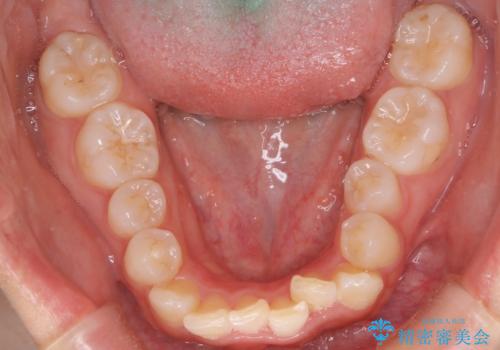

- 歯のデコボコ(叢生)を気にされて来院されました。精密な検査の結果、中等度の叢生と診断。患者様のご希望に合わせ、透明で目立ちにくい**インビザライン(マウスピース矯正)**による治療計画を立案しました。歯を抜かずに、歯列弓(歯が並ぶアーチ)を少しずつ拡大することで、歯が並ぶスペースを確保し、叢生を改善することを目指します。

今回の矯正治療では、透明なマウスピース型の装置インビザラインを使用しました。この装置は目立ちにくく、取り外しが可能なため、食事や歯磨きも普段通りに行えます。治療は、緻密に計算された治療計画に基づき、段階的に作製されたマウスピースを交換していくことで、歯列弓全体を徐々に広げていきました。この歯列弓の拡大により、不足していたスペースを確保し、歯のデコボコを効果的に解消。抜歯することなく、整った美しい歯並びと良好な咬み合わせを獲得していただけました。